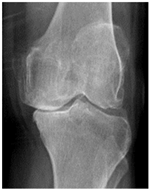

In the local dataset, we have selected 60 adult patient files of men and women with knee disorders who were radiographically examined at the Radiology Department of the El Kelaa des Sraghna Provincial Hospital. Each file consists of one or more knee radiographs in Dicom format as presented in Figure 7. The images were acquired using a standard ITALRAY radiology table. After analysis, 30 images with implants and non-posterior-anterior examination views were excluded and 30 left and right Dicom knees were retained to validate this work. To make the validation local dataset, the ROI was selected manually as illustrated in Figure 8. Then, each patient’s file was presented to a rheumatologist with PNG images. In case of disagreement between our diagnostic system and the rheumatologist, a radiologist was consulted for arbitration to make the final decision.

Figure 7.

Example of knee X-ray images collected and filtered from patients with knee symptoms.